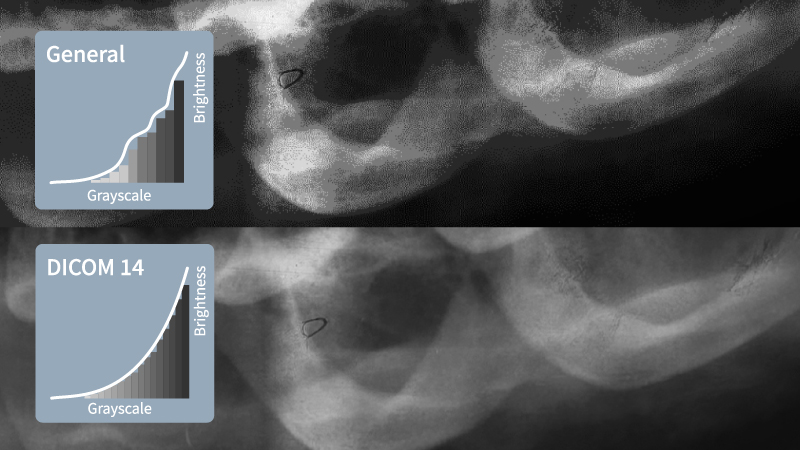

Comparison between a dental monitor and a consumer-grade monitor showing dental X-ray clarity. Dental monitors provide sharper grayscale rendering.

For dental digital imaging, DICOM compliance is a fundamental requirement. X-ray and CBCT images follow the DICOM standard, ensuring that grayscale tones, brightness, and contrast are rendered accurately for proper diagnosis.

A monitor without DICOM mode cannot properly display these images, leading to incorrect brightness levels, contrast inconsistencies, and loss of critical details. Without DICOM compliance, radiographic images may appear too bright or too dark, making it difficult to assess bone structures, root conditions, and periodontal health accurately.

While DICOM compliance is essential, it alone is not enough to guarantee optimal diagnostic accuracy. The monitor’s grayscale performance, bit depth, and color accuracy also play a critical role in accurately interpreting dental images.

In contrast, dental imaging displays are DICOM Part 14 compliant, ensuring precise grayscale accuracy. This allows for consistent and reliable rendering of radiographs, improving diagnostic confidence and reducing the risk of misdiagnosis.